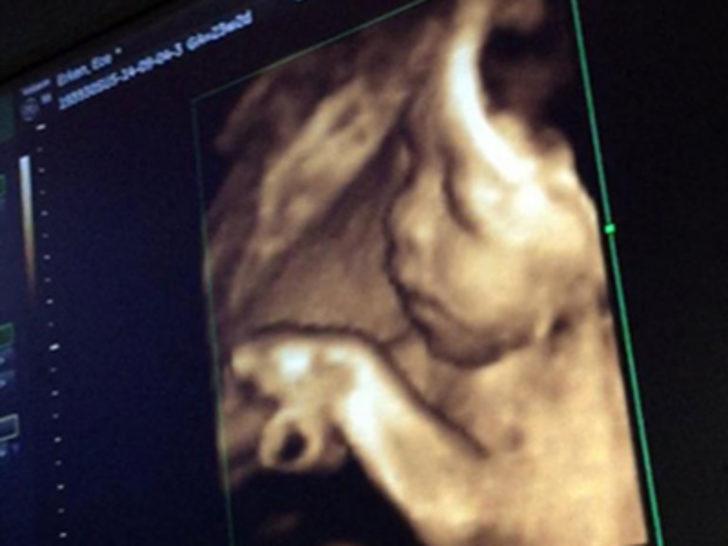

Ece Erken, dün oğlunun ultrason fotoğrafını 'Eymen, karnımdayken... Telefonum kırılmıştı yeni ulaştım fotoğraflara ne günlerdi. Tüm hamilelere selam olsun... Çok çabuk geçiyor zaman çok...' notuyla paylaşınca bazı takipçilerinin tepkisiyle karşılaştı.

Erken'i 'neden senin için özel olan anları internette paylaşıyorsun, bu olmadı şimdi' şeklinde eleştiren takipçileri fotoğrafı kaldırmasını istedi.